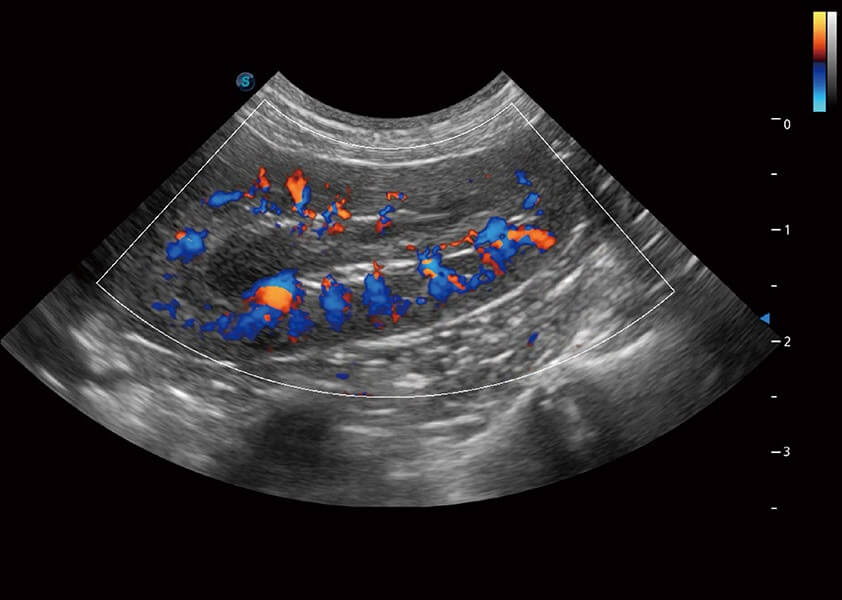

ProPet 60 作为一款高端台式动物超声设备,为动物医生的日常诊断提供了一系列贴合动物临床需求、解决临床实际问题的高级成像功能。凭借全系列高清探头,满足医生对腹部、心脏、生殖、浅表、肌骨等成像的所有需求,切实帮助您提升检查效率,提高诊断信心。

兽用彩色多普勒超声诊断系统

动物是人类最亲密的朋友和最值得信赖的伙伴。竞技宝(JJB)官方网站也一直致力于探索动物专用的超声影像解决方案。 全新推出的ProPet系列,是竞技宝(JJB)官方网站在动物超声影像智能化、专业化、精准化的一次跨越式革新。动物不能用言语来表述自己的不适,通过超声影像,ProPet系列搭建了动物医生与不同物种沟通的“桥梁”,为动物医生注入了“治愈之力”。